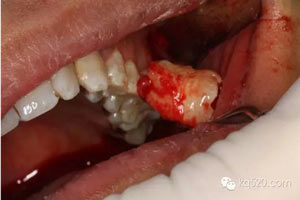

圖10. 28牙齒被完整取出來。

圖11.取出來的28牙齒。